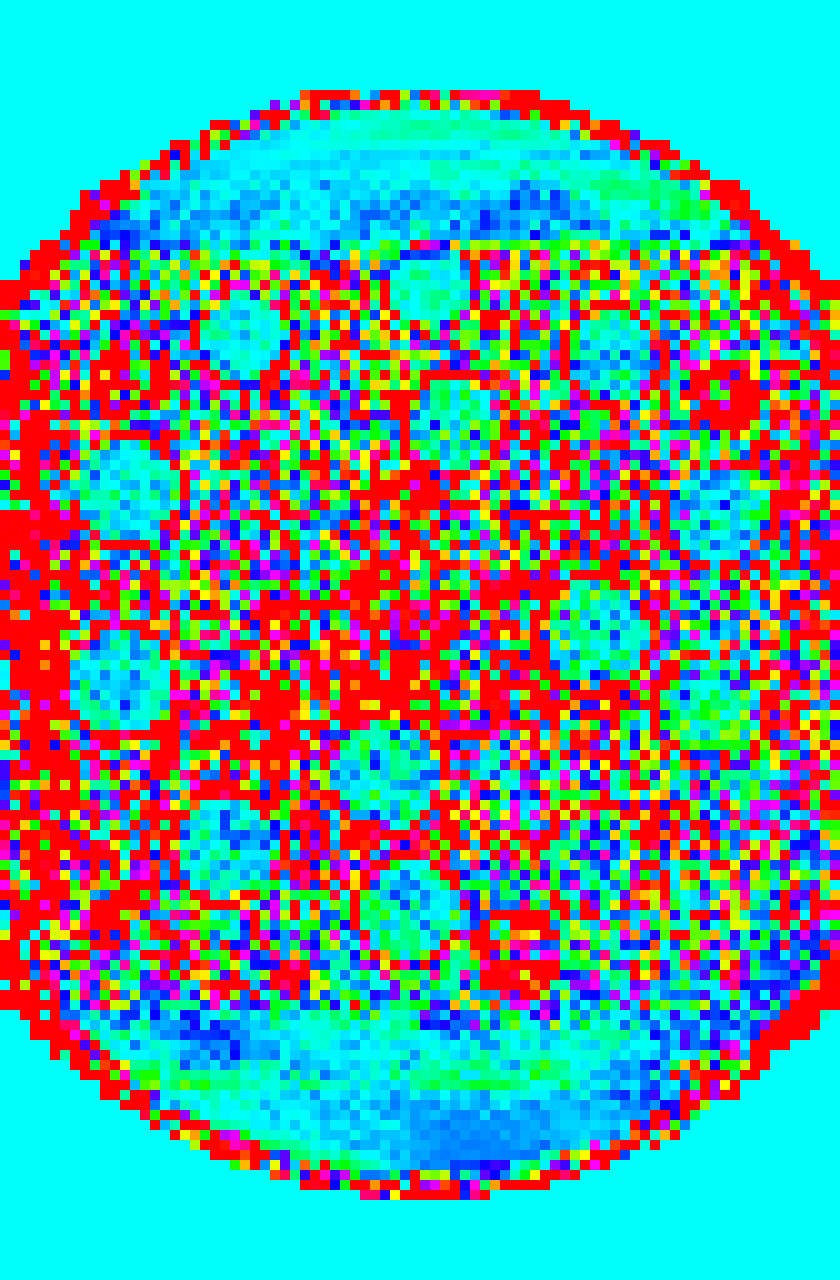

To obtain realistic ground truth parameter maps we performed a fully sampled scan of the Eurospin II T05 (Diagnostic Sonar LTD, Livingston, Scotland) with sequence settings described in Section 3.1 and a 3.03.03.0 T clinical scanner (Discovery MR750, GE Healthcare, Waukesha, WI) using an 8-channel head coil. As performing a fully sampled acquisition on both phase encoding directions takes an impractically long scan time, the acquisitions were performed with a reduced acquisition matrix of size 8×64×1288641288\times 64\times 128 in PE2(SI)×PE1(LR)×FE(AP)𝑃subscript𝐸2𝑆𝐼𝑃subscript𝐸1𝐿𝑅𝐹𝐸𝐴𝑃PE_{2}(SI)\times PE_{1}(LR)\times FE(AP). Only the central slice of the reduced PE2𝑃subscript𝐸2PE_{2} dimension was selected for further processing. This slice will be used as if it was acquired along the PE1𝑃subscript𝐸1PE_{1} and PE2𝑃subscript𝐸2PE_{2} dimensions for the experiments in the following sections. The eight coil sensitivity maps C𝒙,cGTsubscriptsuperscript𝐶𝐺𝑇𝒙𝑐C^{GT}_{\bm{x},c} were computed from the first contrast of the fully sampled scans using the ESPIRIT technique [44] and the BART toolbox [45]. Subsequently, the parameter maps used as ground truth, 𝜽𝒙GTsubscriptsuperscript𝜽𝐺𝑇𝒙\bm{\theta}^{GT}_{\bm{x}}, were estimated by least squares fitting of fq(θ𝒙)subscript𝑓𝑞subscript𝜃𝒙f_{q}(\theta_{\bm{x}}) to each voxel of the contrast images.

Refer to caption

(a) Full-size magnitude of M0subscript𝑀0M_{0} map

(b) Downsampled magnitude of M0subscript𝑀0M_{0} map

(c) Full-size phase map of M0subscript𝑀0M_{0}

(d) Downsampled phase map of M0subscript𝑀0M_{0}

(e) Full-size T1subscript𝑇1T_{1} map (ms)

(f) Downsampled T1subscript𝑇1T_{1} map (ms)

(g) Full-size T2subscript𝑇2T_{2} map (ms)

(h) Downsampled T2subscript𝑇2T_{2} map (ms)

Fig. 2: The ground truth maps acquired from a fully sampled acquisition of the Eurospin II TO5 phantom used in the Monte Carlo simulations are shown on the left, and downsampled version of the map for computation of TEUSQA is shown on the right.

The 𝜽𝒙GTsuperscriptsubscript𝜽𝒙𝐺𝑇\bm{\theta}_{\bm{x}}^{GT} and C𝒙,cGTsubscriptsuperscript𝐶𝐺𝑇𝒙𝑐C^{GT}_{\bm{x},c} were downsampled to |Ωx,D|=24×24superscriptΩ𝑥𝐷2424|\Omega^{x,D}|=24\times 24 by applying nearest-neighbor interpolation on each parameter map separately while undersampling patterns were generated specifically for Ωx,DsuperscriptΩ𝑥𝐷\Omega^{x,D}. Both the original and downsampled ground truth maps are shown in Figure 2. The ROI mask was obtained by applying the same downsampling operation to 𝜽𝒙GTsuperscriptsubscript𝜽𝒙𝐺𝑇\bm{\theta}_{\bm{x}}^{GT}, to the ROI mask used for Monte Carlo simulation. The ηpsubscript𝜂𝑝\eta_{p} for each voxel corresponding to voxels in the full-size map where nominal values are available was computed according to Equation 14.